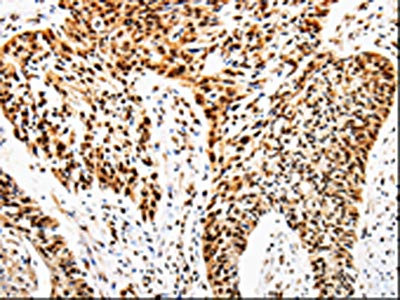

The image is immunohistochemistry of paraffin-embedded Human cervical cancer tissue using CSB-PA261295(ANGPTL4 Antibody) at dilution 1/25. (Original magnification: ×200)

The image is immunohistochemistry of paraffin-embedded Human esophagus cancer tissue using CSB-PA261295(ANGPTL4 Antibody) at dilution 1/25. (Original magnification: ×200)